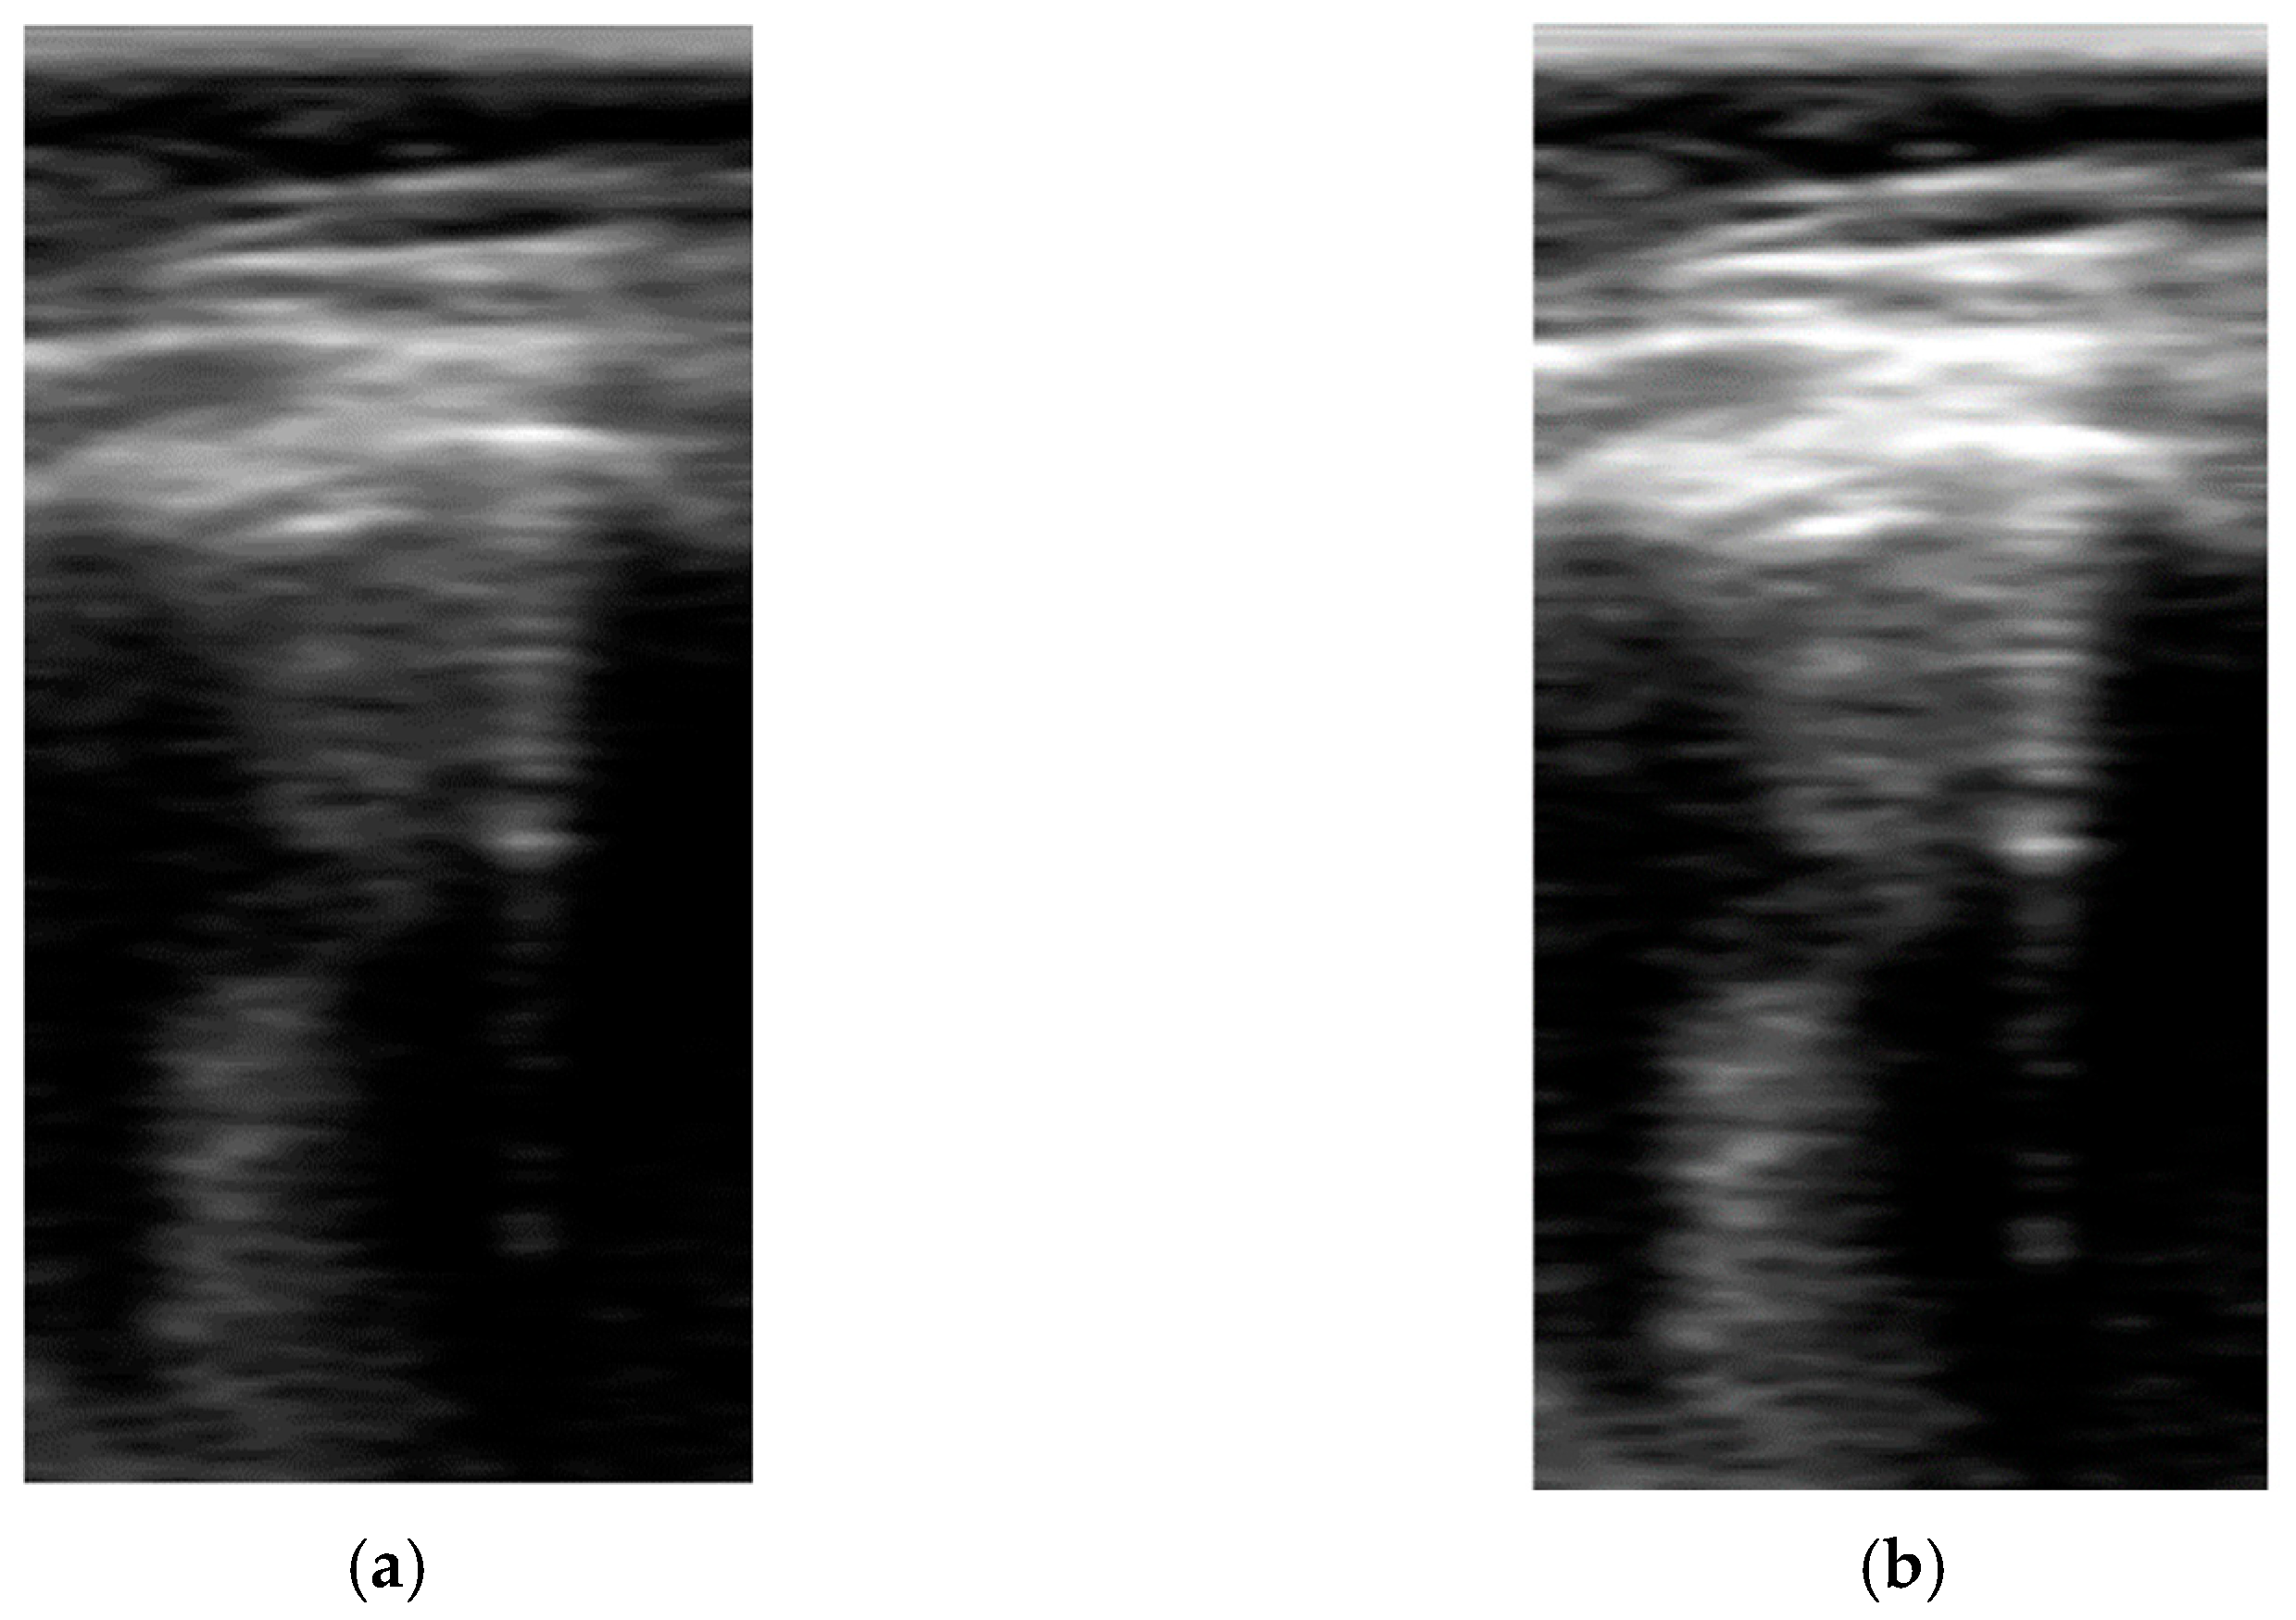

Pre-Processing Block

Model Prediction